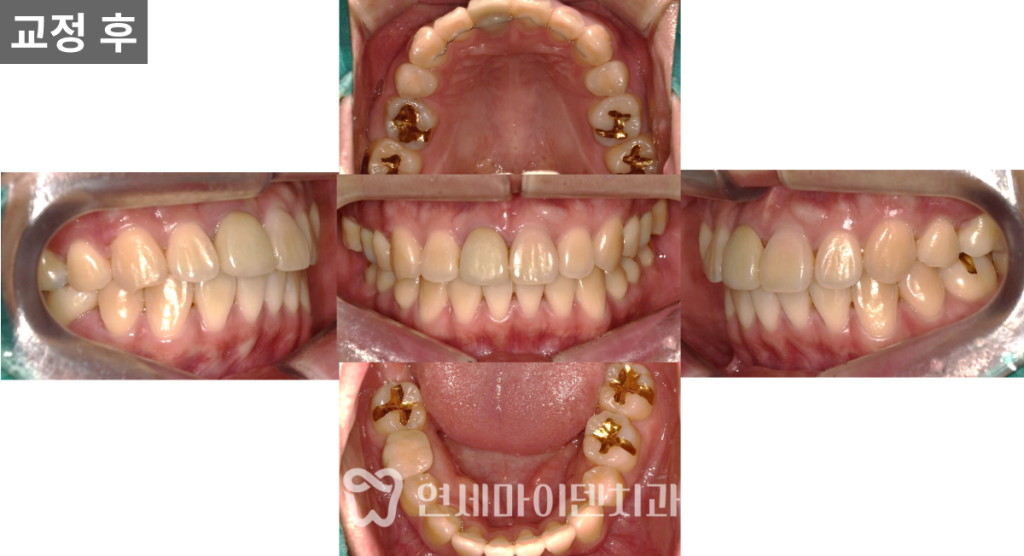

치료 완료 (2년 9개월)

최종적으로 모든 발치 공간이 닫히고

치아 배열은 안정적으로 정리되었습니다.

- 발치 부위는 보철 치료를 통해 대칭성 확보

- 어금니 교합 안정적으로 회복

- 돌출된 앞니가 후방으로 이동하며 입술 돌출 개선 확인

교정 전후 변화

염증과 불완전한 신경치료가 있었던 치아를 발치하고

사랑니까지 함께 정리한 뒤 교정을 진행했습니다.

치료 종료 시점에서는 뿌리 흡수 없이

안정적인 상태로 마무리되었습니다.

앞니 배열이 가지런해졌고,

측면에서는 입술 돌출이 개선되어

보다 조화로운 얼굴 라인을 확인할 수 있었습니다.